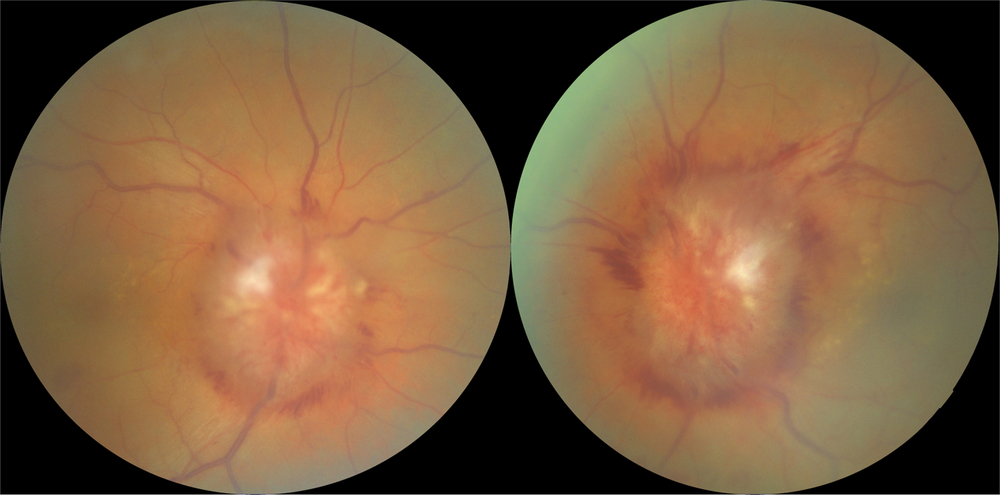

A 61-year-old male was referred for assessment of bilateral optic disk edema, which was noticed 3 months ago when he complained of slow progressively worsening vision in both eyes. At that time, visual acuity was recorded as 20/25 on the right and 20/30 on the left. Around the same time, the patient was diagnosed with stage IV poorly differentiated gastric adenocarcinoma. Enlarged perigastric lymph nodes and diffuse bony metastasis were present at the time of diagnosis. After bilateral optic nerve head edema was confirmed, a contrast-enhanced magnetic resonance imaging (MRI) of the brain was performed and interpreted as normal. MRI of the spine demonstrated diffuse osseous metastases. High-volume lumbar puncture (LP) demonstrated mildly elevated leukocyte count and protein levels but no evidence of malignant cells on cytological analysis. Systemic chemotherapy was commenced. Visual acuity continued to deteriorate and the patient was referred to our service 3 months later. Visual acuity was 20/50 in each eye, there was no relative afferent pupillary defect, and formal visual fields demonstrated marked generalized depression in both eyes. There was bilateral severe optic nerve head swelling (Figure 1). Neurologic exam demonstrated a wide-based gait and slightly decreased strength in the left leg.

Figure 1: Fundus photographs demonstrating severe bilateral optic nerve head swelling.

Our patient was found to have bilateral optic nerve head swelling which was initially presumed to be caused by papilledema due to increase in CSF viscosity. However, severely constricted visual fields and the presence of diffuse leptomeningeal thickening and enhancement surrounding intraorbiral optic nerves on imaging suggested bilateral optic neuropathy due to compression of the optic nerves by metastatic deposits as an additional mechanism of optic nerve swelling. The presence of papilledema was supported by relative preservation of central visual acuity despite long-standing disk edema as well as an elevated opening pressure on LP. There are several proposed mechanisms for increased intracranial pressure in patients with LC: it may be secondary to high levels of CSF protein due to leptomeningeal seeding by cancer cells which increases CSF viscosity and leads to its decreased outflow. Another possibility is cerebral edema secondary to increased cerebral vascular endothelial permeability due to aberrant stimulation of the meninges by tumor cells causing release of various chemical mediators Reference Nayar, Ejikeme and Chongsathidkiet6 . Lastly, tumor cells may directly block arachnoid granulations, the presumed main site of CSF absorption.

Second mechanism for marked bilateral disk edema in our patient was most likely a superimposed bilateral optic neuropathy as demonstrated by constricted visual fields and slowly deteriorating central visual acuities. This was most likely secondary to infiltration of subarachnoid space around the optic nerves by malignant cells causing compression of the optic nerves. This process is more plausible as opposed to direct infiltration of the optic nerve by cancer cells, which typically produces very quickly deteriorating vision resulting in catastrophic visual loss.